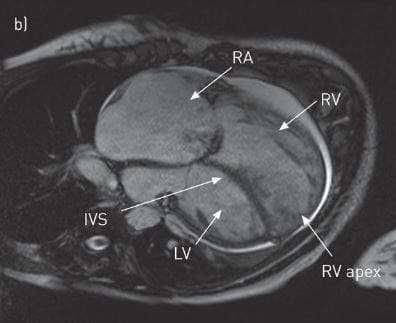

The new Precession system, developed by Heart IT, allows physicians at different locations to simultaneously view CMR images and interact with each other simply by logging onto a secure website. The Precession system also displays results as the images are being viewed, populating report fields to help maximize efficiency and streamline workflow. Ejection fraction, left ventricle and right ventricle volumes and other measurements aid in accurately interpreting complicated examinations quickly. The system also uses an automated email function to deliver images and reports to referring physicians.